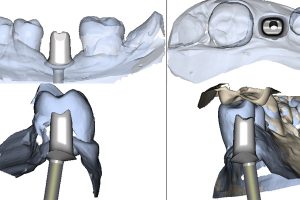

- Ryc. 19_Wirtualny obraz planowanego łącznika dla systemu Atlantis C/X w oprogramowaniu ATLANTIS-VAD.

- Ryc. 20_Projekt łącznika Atlantis w stosunku do zębów przeciwstawnych widoczny w oprogramowaniu ATLANTIS-VAD.

Po zamontowaniu tzw. skan lokatorów i zeskanowaniu modelu, wypełniany jest formularz zamówienia na łącznik. Zawiera on wszystkie niezbędne informacje dotyczące sposobu wykonania łącznika zgodnie z życzeniem zamawiającego takie, jak: rodzaj materiału, kompresja tkanek miękkich, profil wyłaniania, angulacja, wysokość okluzyjna, głębokość posadowienia poddziąsłowo stopnia dla korony itp. Następnie formularz ten (tzw. Atlantis WebOrder) łącznie ze skanami przesyłany jest do Centrum Projektowania i Frezowania Atlantis. W odpowiedzi na zamówienie otrzymujemy wirtualny projekt łącznika do akceptacji w programie Atlantis VAD. W zależności od tego, czy projekt spełnia nasze oczekiwania, czy też wymaga zmian, do Centrum Projektowania wysyłana jest określona informacja. Po ostatecznym za- akceptowaniu projektu łącznika, zamówienie otrzymuje status realizacji i łącznik przekazy- wany jest do produkcji. Po kilku dniach łącznik trafia do laboratorium, gdzie jest sprawdzany na modelach gipsowych i odsyłany do kontroli klinicznej.